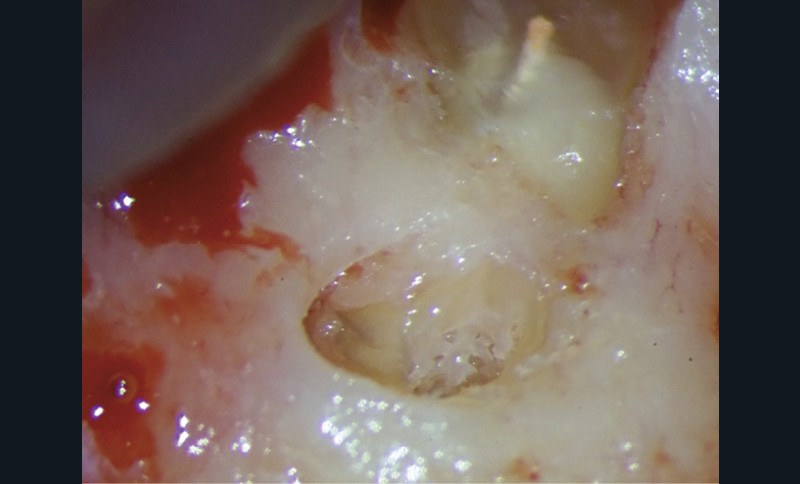

Le laser Er:YAG va permettre une élimination des débris en surface, une stérilisation, avec comme irrigation de l’eau stérile [36] et en coupant le spray, une hémostase avec la formation d’une couche de coagulation [37] propre à la formation d’un pont dentinaire au contact du biomatériau, qui peut être bio-actif, tel que la Biodentine (Septodont) (fig. 6a à d).

Protocole opératoire : sous anesthésie, une cavité suffisante à recevoir le biomatériau (2 à 3 mm) sous champ opératoire est réalisée. La désinfection au laser Er:YAG (40 mJ ; 20 Hz) sous spray, pendant 20 secondes, est alors mise en œuvre. S’en suit éventuellement une coagulation de 3 secondes, en coupant le spray, puis la mise en place du biomatériau Biodentine (Septodont). Il sera ensuite recouvert d’un matériau de restauration adéquate.